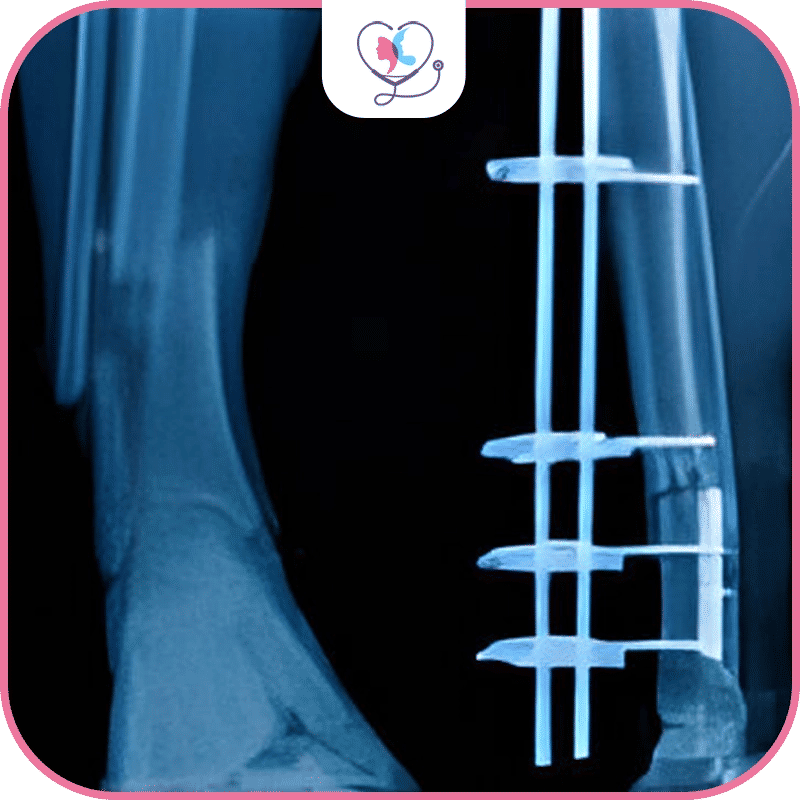

تهدف عملية زيادة الطول إلى تطويل القامة، ويمكن إجراؤها على عظام الفخذين أو الساقين، وإذا كان لديك الرغبة في الحصول على المزيد من الطول حتى 13 سنتيمتر يكون ذلك عن طريق إجرائها على عظام الساق ثم على عظام الفخذين أيضاً أو العكس، ويفصل بينهما فترة زمنية يحددها الطبيب.

عملية تطويل القامة إجراءاً تجميلاً لمن يرغبون في زيادة طولهم بضعة سنتيمترات، أو إجراءاً طبّياً في حالات التقزم الشديد أو التباين في طول الساقين والذي يسبب اختلال التوازن عند المشي، وفي تصحيح حالات التشوهات الهيكلية، وتصليح كسور العظام التي التئمت بشكلٍ خاطئ.